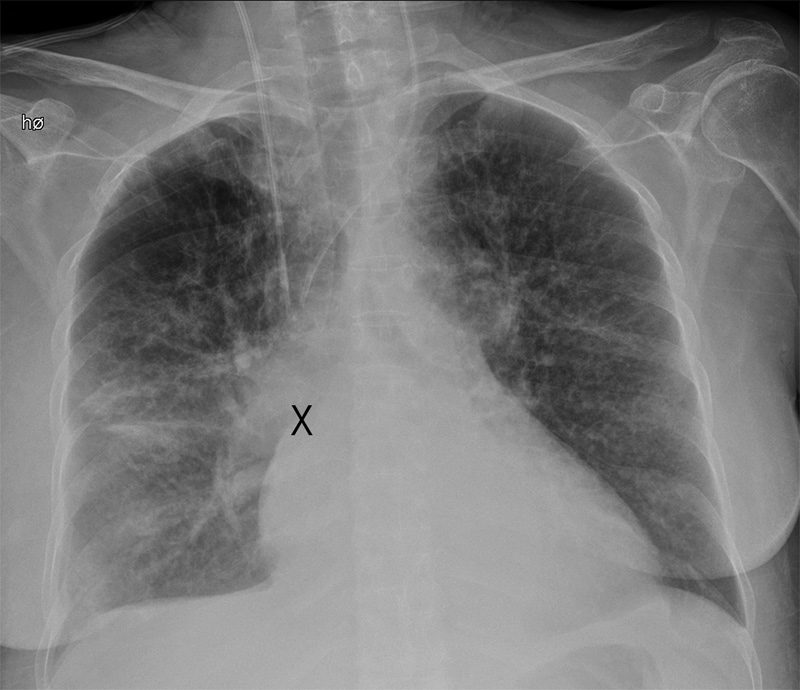

Muligheten for at spissen på det sentrale venekateteret likevel kunne ligge arterielt, ble avkreftet ved ny granskning av røntgen thorax-bildet samt at elektronisk trykkmåling via kateterlumen viste venøse trykknivåer.

Pasienten ble respiratorbehandlet i totalt åtte døgn pga. respirasjonssvikt. Hun ble på overvåkingsavdeling ytterligere seks dager pga. svært dårlig allmenntilstand og utvikling av hjertesvikt med dyspné, pleuravæske og deklive ødemer. Ved overflytting til sengepost var hun fortsatt kraftløs og med behov for parenteral ernæring. Flere kirurgiske tilsyn og bildediagnostikk konkluderte med paralytisk ileus. På sengepost ble det pga. rubor rundt innstikkstedet lagt et nytt sentralt venekateter. Første forsøk på innstikk, nå via venstre v. jugularis interna, ble avbrutt fordi anestesilegen fikk lyst rødt blod tilbake ved aspirasjon og antok at han hadde kommet inn i en arterie. Nytt innstikk ble gjort under ultralydveiledning, og man så da ingen spor etter blødning fra eventuell perforasjon av arterie. I ettertid er det rimelig å anta at også første forsøk var vellykket, men at uventet aspirasjon av arterielt farget blod ble feiltolket av en lege som ikke kjente til pasientens forhistorie. Blodprøver tatt fra dette tredje kateteret, der spissen vurdert røntgenologisk lå på samme sted som nr. 2 (fig 1), viste vedvarende tilnærmet identiske verdier venøst som prøver tatt arterielt, rundt 95 %. Pasienten ble derfor henvist til CT angiografi for å avklare mistanken om sentral arteriovenøs shunt. Undersøkelsen påviste en sjelden anatomisk anomali der venstre pulmonalvenes ene gren drenerte direkte til tverrvenen, vena brachiocephalica sinistra (fig 2, fig 3). Det var gjennom innleggelsen tatt flere røntgen thorax, men ingen av disse kunne gi mistanke om en slik anomali.

Det første kateteret lå lengst distalt i v. cava superior, slik at man kunne tenke seg at kraftig refluks fra en atrieseptumdefekt kunne gi den høye ScvO₂-verdien. De to neste katetrene lå imidlertid mer proksimalt i v. cava superior, og en høy sentralvenøs metning herfra kan vanskelig forklares av en slik årsak (fig 1).